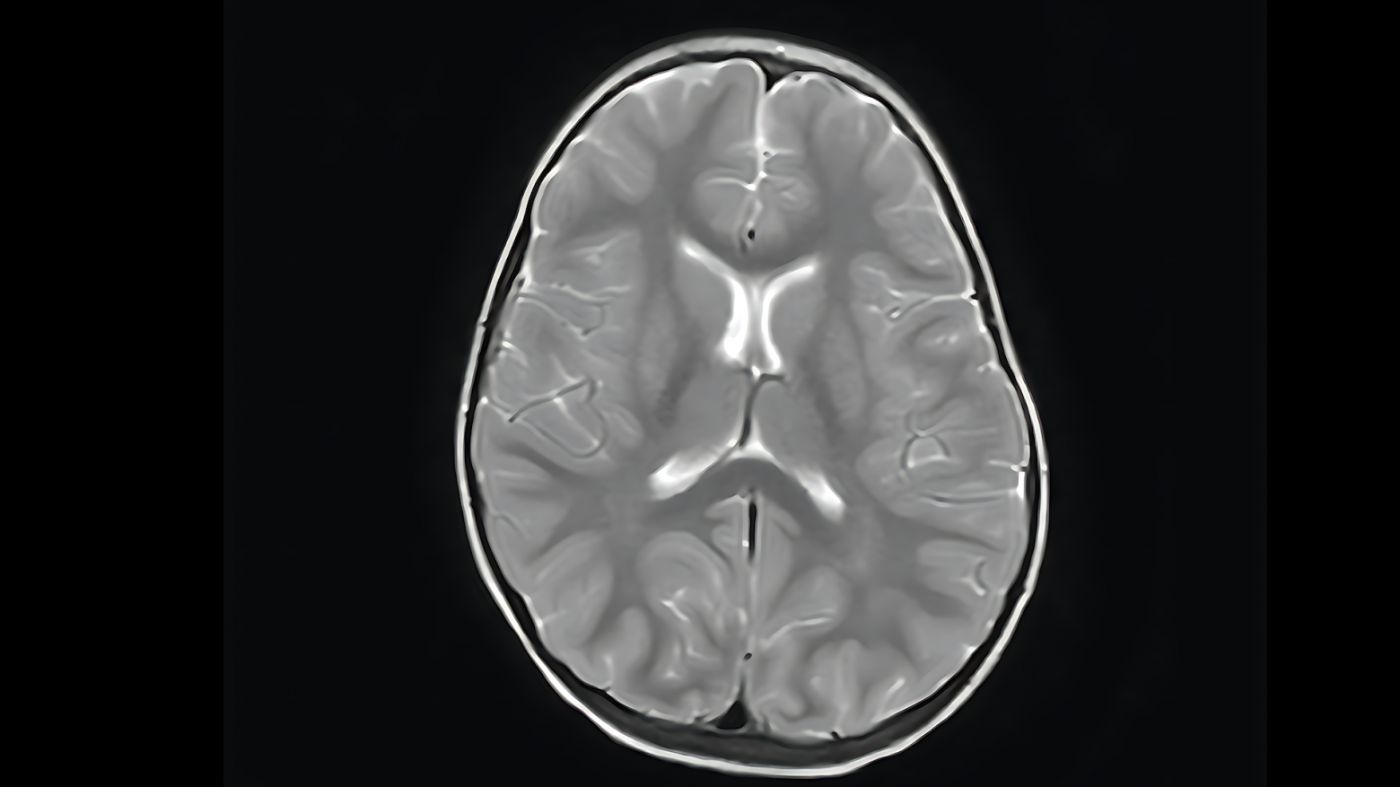

Here's how the model performs on the validation set. Original study from the validation set:

\

Example output from the algorithm

Final metrics:

| \n | iou void | iou GM | iou WM | iou mean | |----|----|----|----|----| | unetresnext5032x4ddice1 | 0.981 | 0.629 | 0.501 | 0.703 |

The inference speed of the trained neural network running on a CPU is about 3 seconds.